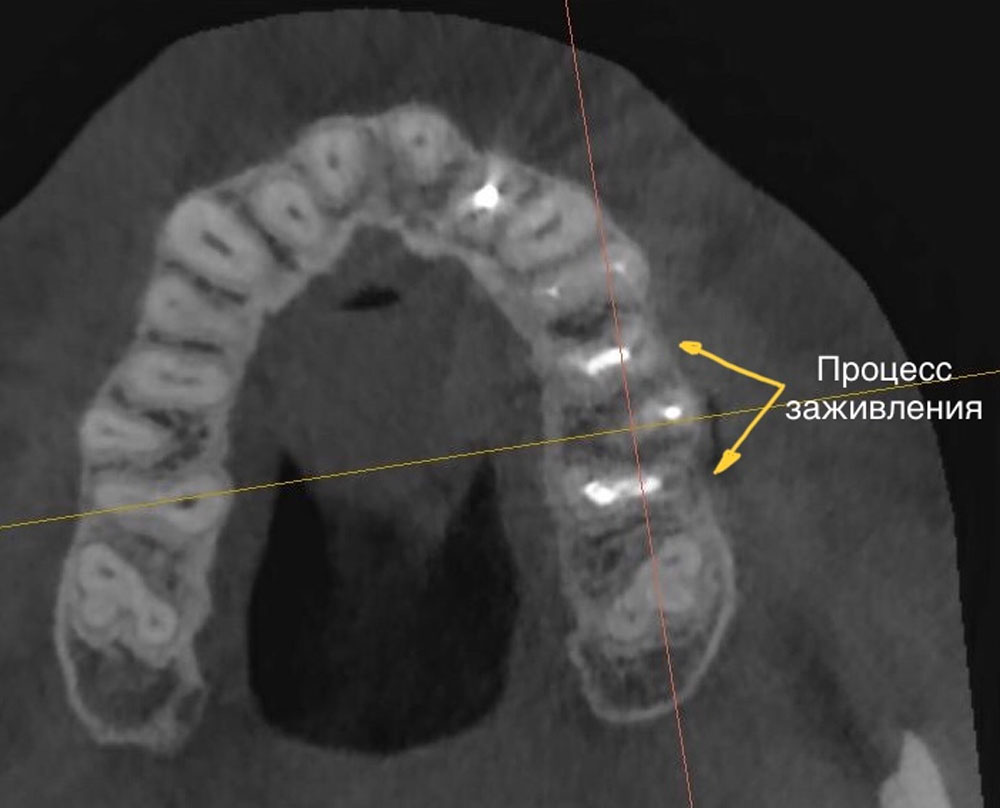

Сразу после операции проводится прицельный снимок и компьютерная томограмма для оценки качества ретроградного пломбирования системы корневых каналов, а также клиническая фотография послеоперационных швов.

Через 6 месяцев на прицельных снимках и компьютерной томограмме отмечается полное заживление костной ткани, губчатого и кортикального слоя.